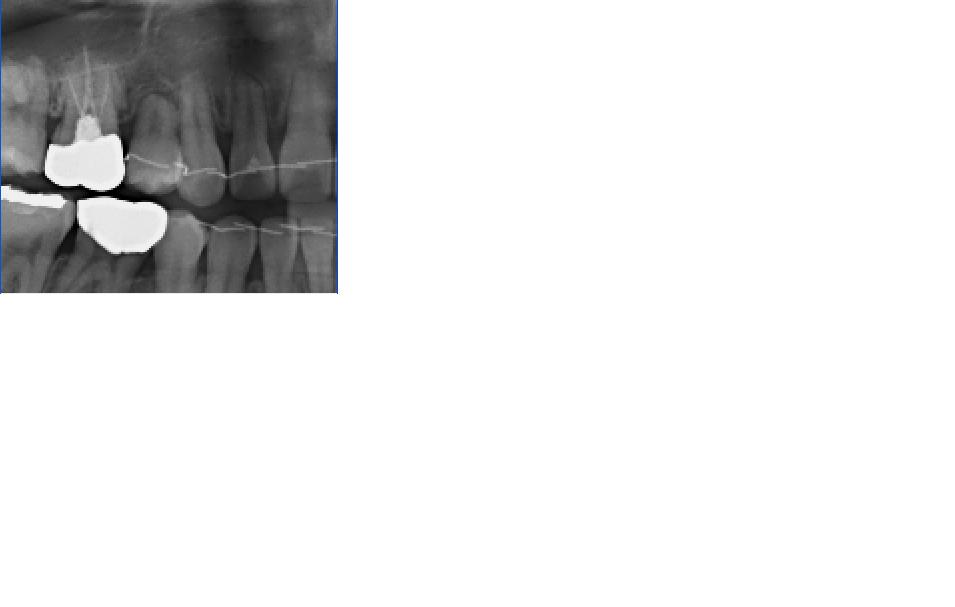

발치후 씹는데에 너무 큰 불편함이 생겼습니다..

안녕하세요... 제가 유전적으로 치아가 많이 없는 상태였습니다.. 플러스로 유치가 있는 상태였어요... 하악 양 옆 어금니가 하나씩 없었고 그 옆에 유치가 하나씩 있었죠.. 이번에 교정을 시작하면서 유치들을 빼니 ...